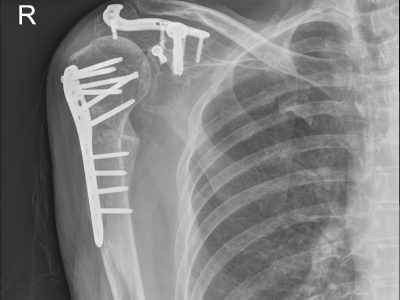

Παρακάτω παρατίθενται ακτινογραφίες καταγμάτων του άνω άκρου που αντιμετωπίζονται με εσωτερική οστεοσύνθεση ή επανορθωτική χειρουργική με αρθροπλαστική.

2. Αντιμετώπιση σύνθετων καταγμάτων βραχιονίου, ωμογλήνης, ωμοπλάτης και κλείδας.

3. Κατάγματα /εξαρθρήματα ώμου και αγκώνα που χρήζουν αντιμετώπισης με Αρθροπλαστική.